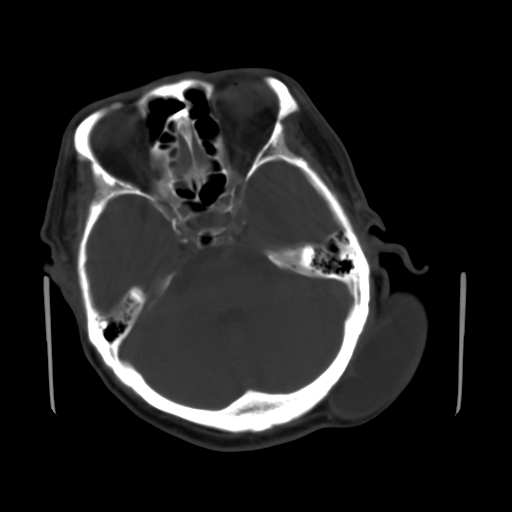

标题: CT25147:男,62岁,右侧肢体活动障碍不灵活三天。 [打印本页]

男,62岁,右侧肢体活动障碍不灵活三天,左侧头皮肿物十余年(ct值8hu)。

1)多发性腔隙性脑梗塞。2)脑白质病。3)脑萎缩。4)左侧枕顶部头皮下皮样囊肿,不排除脂肪瘤。

1)多发性腔隙性脑梗塞。2)脑白质病。3)脑萎缩。4)左侧枕顶部头皮下皮样囊肿或表皮样囊肿。